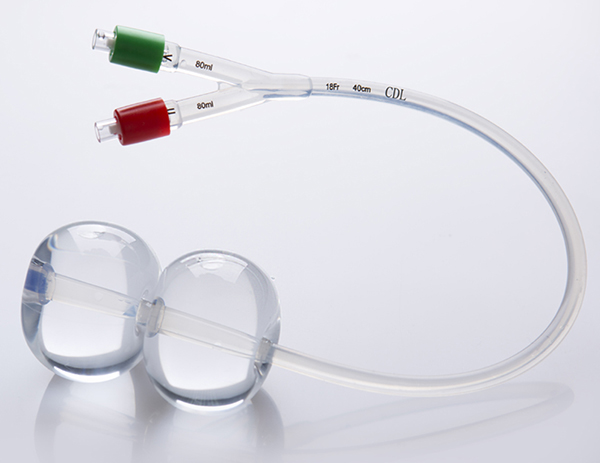

一次性使用子宮頸擴(kuò)張球囊